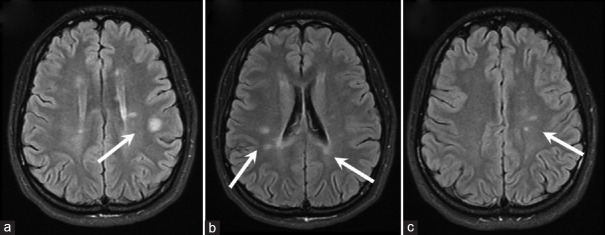

多发性硬化症(MS)是影响中枢神经系统的最常见的脱髓鞘疾病。它的表现多种多样,通常会影响视觉系统。许多多发性硬化症患者会出现视力下降、复视、眼球震颤和眼球运动异常。然而,双侧水平凝视麻痹却极为罕见。我们为大家介绍一例 24 岁女性患者的病例,她来到我们的儿童眼科门诊就诊,主诉双侧水平凝视麻痹、畏光和眼痛 2 天。虽然患者有多发性硬化症家族史,但没有类似或既往的主诉,既往病史和手术史也不突出。检查发现,她的双侧水平囊回和追视功能完全丧失,垂直囊回和追视功能稍有受限。她没有眼球震颤或偏斜,其他颅神经(CN)完好无损。她的眼部生命体征正常,矫正视力为 20/20,全色觉。其他身体和神经系统检查均无异常。转到神经内科后,磁共振成像显示深部白质、脑桥和中脑有多处高强度病变。成像结果与临床表现的相关性证实了临床孤立综合征的诊断。经过脉冲类固醇治疗和五次血浆置换后,患者的眼外肌运动(EOM)明显好转,但同时出现了35棱镜屈光度的后天性内斜视。她接受了右内侧直肌肉毒毒素注射,病情得到明显改善,并在注射后的最后两个月随访中实现了视力矫正。

Multiple sclerosis (MS) is the most common demyelinating disease affecting the central nervous system. It has a wide range of manifestations and commonly affects the visual system. Many patients with MS report decreased vision, diplopia, nystagmus, and abnormal ocular motility. Nevertheless, bilateral horizontal gaze palsies are exceptionally rarely seen. We present the case of a 24-year-old female who came to our pediatric ophthalmology clinic complaining of bilateral horizontal gaze palsy, photophobia, and eye pain for 2 days. Although the patient had a family history of MS, there was no similar or previous complaint, with an unremarkable past medical and surgical history. During the examination, she was found to have a complete bilateral absence of horizontal saccade and pursuit, with slight limitations in vertical ones. There was no nystagmus or skew deviation, and the rest of the cranial nerves (CNs) were intact. Her ocular vital signs were normal, and her corrected visual acuity was 20/20 with full-color vision. The rest of the physical and neurological examinations were unremarkable. After referral to neurology, the magnetic resonance imaging showed multiple hyperintense lesions in deep white matter, pons, and midbrain. The correlation of imaging findings with clinical presentation confirmed the diagnosis of a clinically isolated syndrome. Extra-ocular motility (EOM) significantly improved after pulse steroid therapy and five sessions of plasma exchange, but the patient developed 35 prism diopter of acquired concomitant esotropia. She underwent a right medial rectus botulinum toxin injection which dramatically improved her condition, and became orthotropic during the last 2 months of follow-up after the injection.